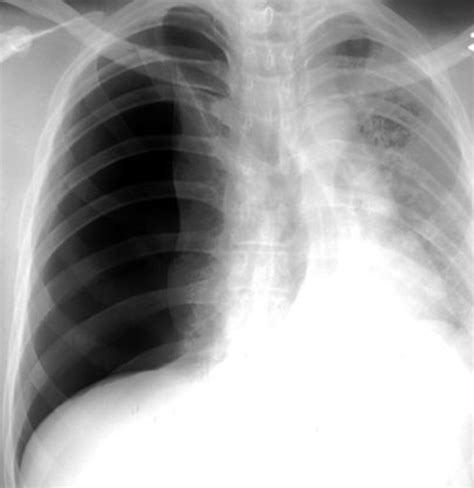

Tension Pneumothorax

A tension pneumothorax is a medical emergency where air continues to accumulate in the pleural space, leading to increased pressure and potential collapse of the lung and mediastinal shift. On an X-ray, it shows a large area of hyperlucency with a deviated mediastinum and flattened diaphragm on the affected side.